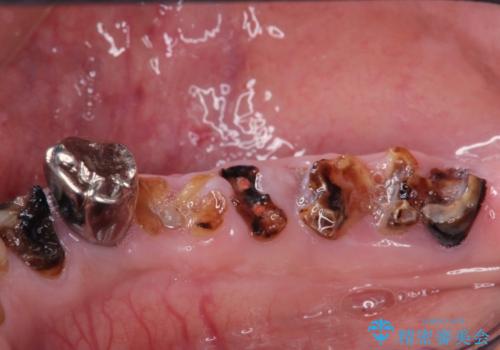

- 色や形、適合の悪いクラウンの再治療を希望され来院されました。

装着されているクラウンを除去し、自然な色調のジルコニアクラウンによる審美生の改善、インプラントを用いた欠損部の機能回復を計画します。

- 88万円(インプラント・チタンカスタムアバットメント・ジルコニアクラウン×4・仮歯×4)費用は治療当時の料金となります